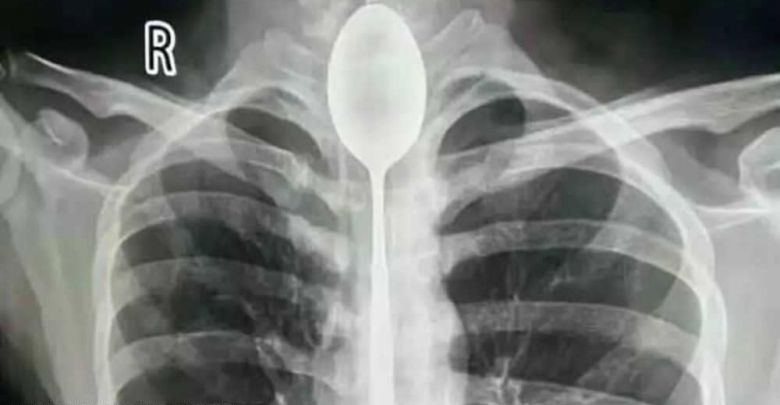

وقام بابتلاع ملعقة معدنية يبلغ طولها 20 سنتيمترا، ولم يفلح في إخراجها، وبقيت عالقة داخل المريء عاما كاملا دون أن تعيقه عن الأكل والشرب بشكل طبيعي، بحسب ما نقلت “سكاي نيوز” عن صحيفة “ديلي ميل” البريطانية.

ومنذ أيام، تعرض الشاب لضربة في صدره، شعر بعدها بآلام وصعوبة في التنفس دفعته للذهاب إلى مستشفى في مقاطعة شينجيانغ الصينية، حيث اكتشف الأطباء وجود الملعقة، التي تسببت بالتهاب في المريء.

وقام الأطباء بإخراج الملعقة عبر تقنية المنظار، مستخدمين أداة تم إدخالها عن طريق الفم، لتلتقط الملعقة وتخرجها، في عملية استغرقت ساعتين.